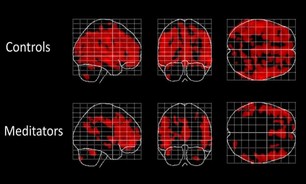

راهکار موثر برای پیشگیری از آلزایمر

به گزارش فرهنگ عجب شیر به نقل از خبرنگاران،در این مطالعه تازه، دکتر Kurth و همکارانش دریافتند ارتباط مستقیمی بین مدیتیشن و جلوگیری از پیری مغز وجود دارد. محققان ۱۰۰ نفر بین ۲۴-۷۷ ساله را مورد مطالعه قرار دادند و دیافتند افرادی که یوگا کار می کنند و مدیتیشن جزو برنامه های آن هاغ است حافظه بهتری دارند. محققان با …